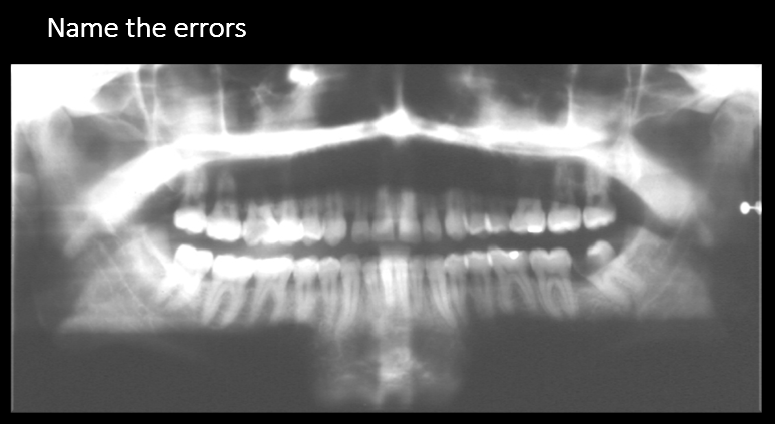

Name the errors

Palatoglossal space

earring ghost image